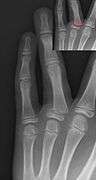

Salter–Harris fracture images

| Salter–Harris fracture radiographs with insets showing fracture lines. | ||||||||